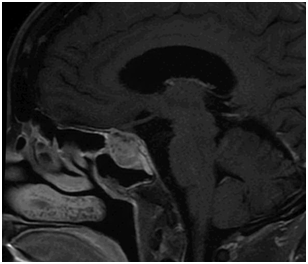

Ophthalmologic exam revealed loss of light perception from the right eye and complete right abducens nerve palsy. She was initially diagnosed with pituitary apoplexy secondary to an enlarging adenoma and was scheduled for immediate surgery. Preoperative testing showed no abnormalities of pituitary endocrine function. The immediate preoperative MRI is shown in Figure 1.

Figure 1 Pre-operative sagittal T1 post-contrast MRI shows a 2.7x2.1x2.0 cm enhancing sellar and suprasellar mass with internal cystic components. There is upward impingement on the optic chiasm and encasement with narrowing of the right cavernous carotid.